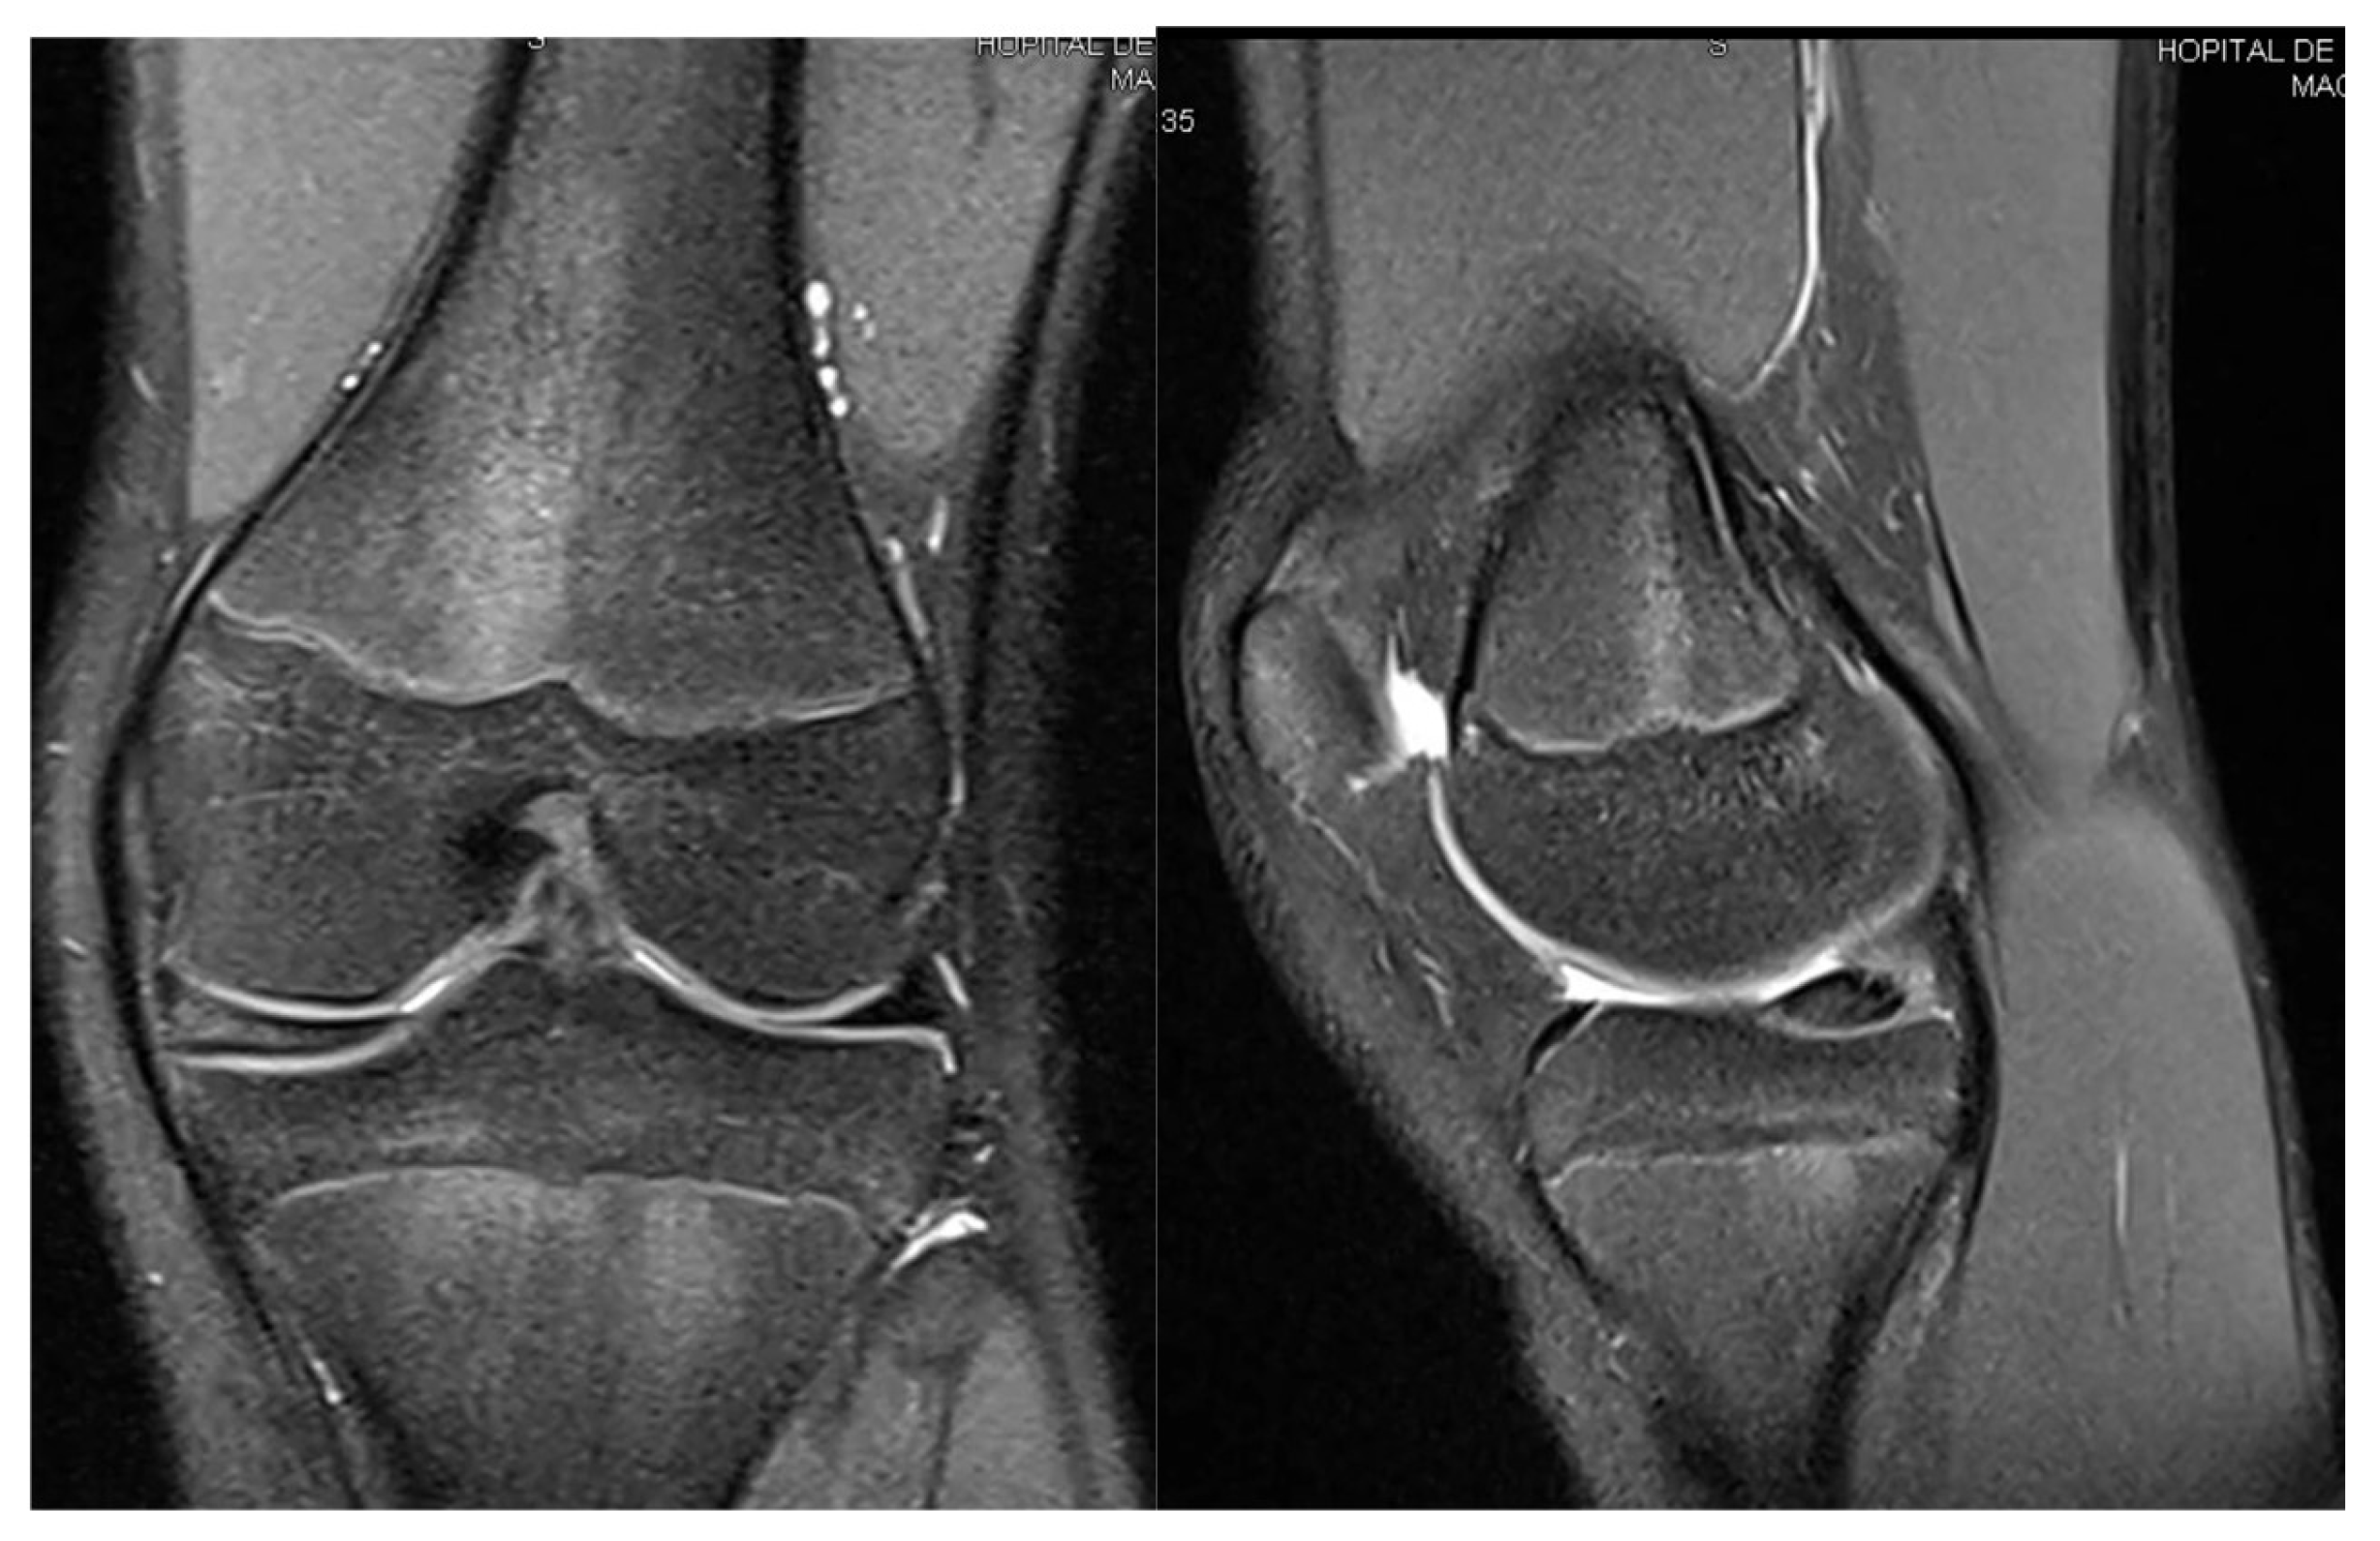

3.1. Case 1—P.E.

3.2. Case 2—S.C.S.

3.3. Case 3—G.L.